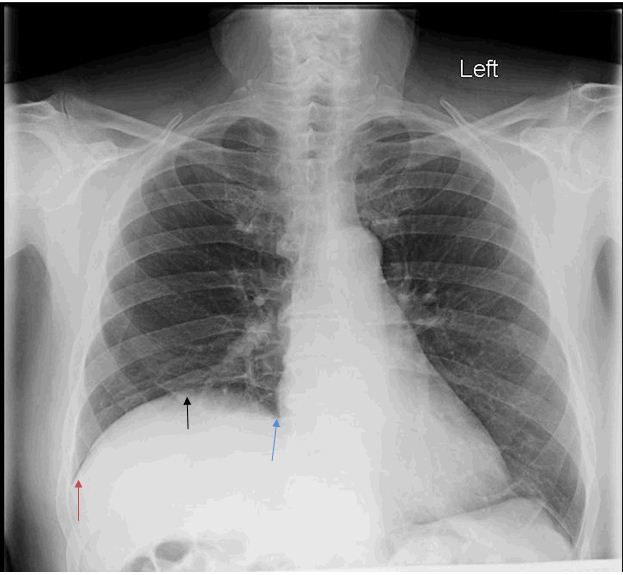

Case Reports in Anesthesia WPW syndrome in patient with significant